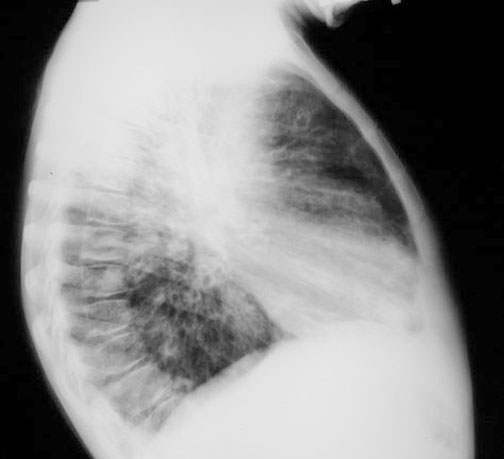

Lateral